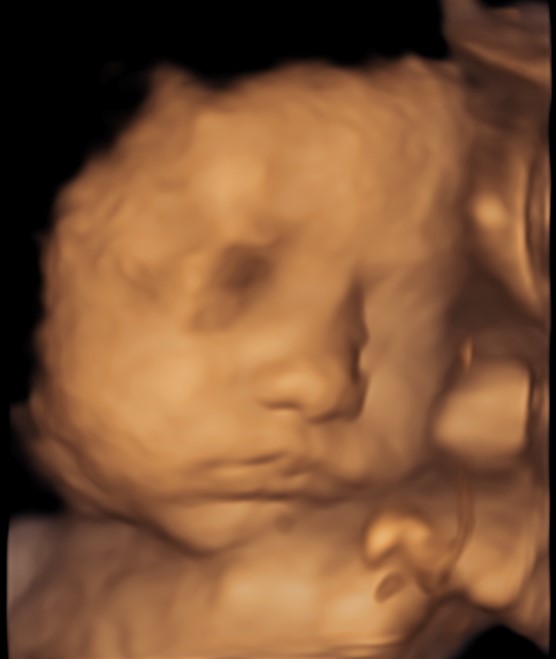

4D/5D/HD Ultrasound Gallery

Gallery